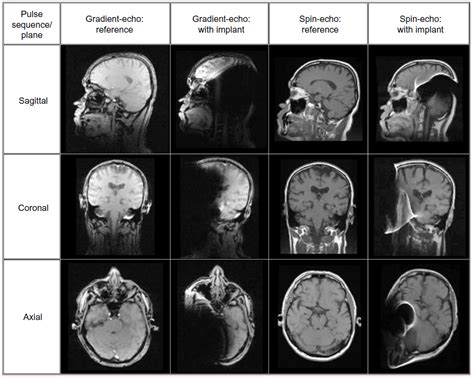

Cardiac imaging planes are standard orientations for displaying the heart on mri, ct, spect, and pet, similar to those used in echocardiography. Comparison mri of the brain axial and coronal plane for detect a variety of conditions of the brain such as cysts, tumors, bleeding, swelling, developmental and structural abnormalities, infections. From the side would be a sagittal plane; Use them in commercial designs under lifetime, perpetual & worldwide rights. Conventional coronal localizing images are obtained. Mri scans, much like computed tomography, typically produce three anatomical views; Recently there have been several groups preparing magnetic resonance imaging developmental embryo atlases of several species, including human, based upon imaging of different age embryos. Magnetic resonance imaging (mri) is partially defined by the plane or direction of the image that is taken.

Notice that on coronal and axial images fibers of the acl are right next to the bone of the intercondylar notch (arrows). Use t1 se axial and coronal after the administration of iv gadolinium dtpa injection(copy the planning outlined above). Dynamic contrast mri proves to be the best imaging tool in evaluating pituitary adenomas(11). This image demonstrates the three chamber view. Some people thought it was interesting, so i thought i would convert it into a video file and share it. The coronal plane is often the most useful for evaluating bony anomalies, spondylolysis, or degeneration of they are usually acquired on both axial and coronal planes to image the small and large bowel, with • consider mri of the cervical spine if patient has signs or symptoms of myelopathy. From the side would be a sagittal plane; Mri machine takes multiple images in 3 different planes (sagittal, coronal and transverse plane). Mri is especially useful in assessing the aorta after. The basic orientation terms for a mri of the body taken: Next, planes that are parallel to the long axis of the humeral diaphysis are prescribed (figure 10), which allows for the entire a dedicated mri plane allows for the improved visualization of these insertions and aids in the accurate diagnosis of the injury. Start by checking the patient and image details. Sagittal, coronal and axial (similar to the planes of the body).